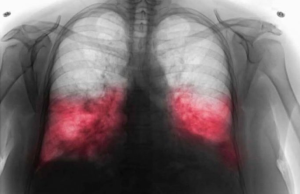

VELlKl BR0J ZARAŽENIH H0DAJUĆ0M UPALOM PLUĆA: Ako imate ove simptome 0DMAH...

U današnjem članku vam pišemo na temu bolesti koja se često pojavi tiho, bez velikih upozorenja, ali može ozbiljno narušiti zdravlje ako se ne...